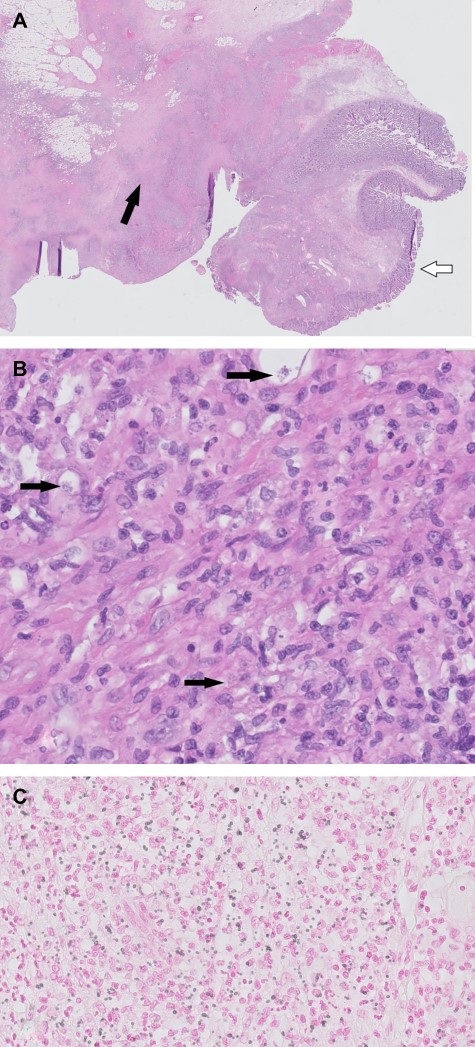

Histopathological images. (A) H&E overview duodenal resection specimen. White arrow: normal duodenal mucosa. Black arrow: inflammation with fibrosis and necrosis. (B) H&E 400×. Black arrows: histoplasmosis. (C) H&E 400×, Grocott staining histoplasmosis.

Unexpectedly, histological examination was not consistent with malignancy but showed signs of yeast and chronic granulomatous inflammation with necrosis, most likely caused by histoplasmosis (Fig. 3). Differential diagnosis included tuberculosis and sarcoidosis. Patient history for such disease was negative; there were no pulmonary symptoms, and travel history in the last decade was negative. Given the pulmonary nodules on initial CT scan and negative sputum tests, a bronchoscopy with bronchoalveolar lavage was performed and Histoplasma capsulatum was found. This confirmed the diagnosis of disseminated histoplasmosis. Given that histoplasmosis rarely occurs in immunocompetent individuals, additional tests for acquired immune deficiency syndromes were performed, revealing a positive human immunodeficiency virus (HIV)-test. The viral load was very high (>10 000 000) with a low CD4 count (CD4% 5 [28–57], CD4 total 20 [560–1490 × 106/l]).

Histoplasma capsulatum is a dimorphic fungus endemic to Central and South America [4]. It is the most common organism in fungal respiratory infections [5]. In healthy hosts, histoplasmosis has a self-limiting course and patients are often asymptomatic. Disseminated histoplasmosis is a rare and life-threatening disease that is mostly found in immunocompromised patients (age extremes, hematologic cancers, use of immunosuppressive medication and untreated HIV with low CD4 levels [<200 cells/ml]) [4–6]. Interestingly, the disease may occur years after exposure, like our patient, who had not been in an endemic area for a decade. It is an acquired immunodeficiency syndrome (AIDS)-defining disease and mortality can be as high as 80% when left untreated [4, 7]. Radiological signs include diffuse nodular or interstitial pulmonary lesions and generalized lymphadenopathy. Pathological findings of gastrointestinal histoplasmosis include mucosal ulceration, diffuse lymphohistiocytic infiltration of the bowel wall (Fig. 3), submucosal nodules, polypoid lesions and obstructing masses [5, 8]. Enzyme immunoassay (EAI) is a rapid and reliable test for disseminated histoplasmosis by detection of the antigen in urine or serum with a sensitivity of 90% [4, 5]. It may also be used during follow-up to monitor therapy efficacy. The management of our patient with severe histoplasmosis is according to international guidelines: initial therapy with lipid formulation of amphotericin B and once patients improve clinically, this should be switched to itraconazole [4].